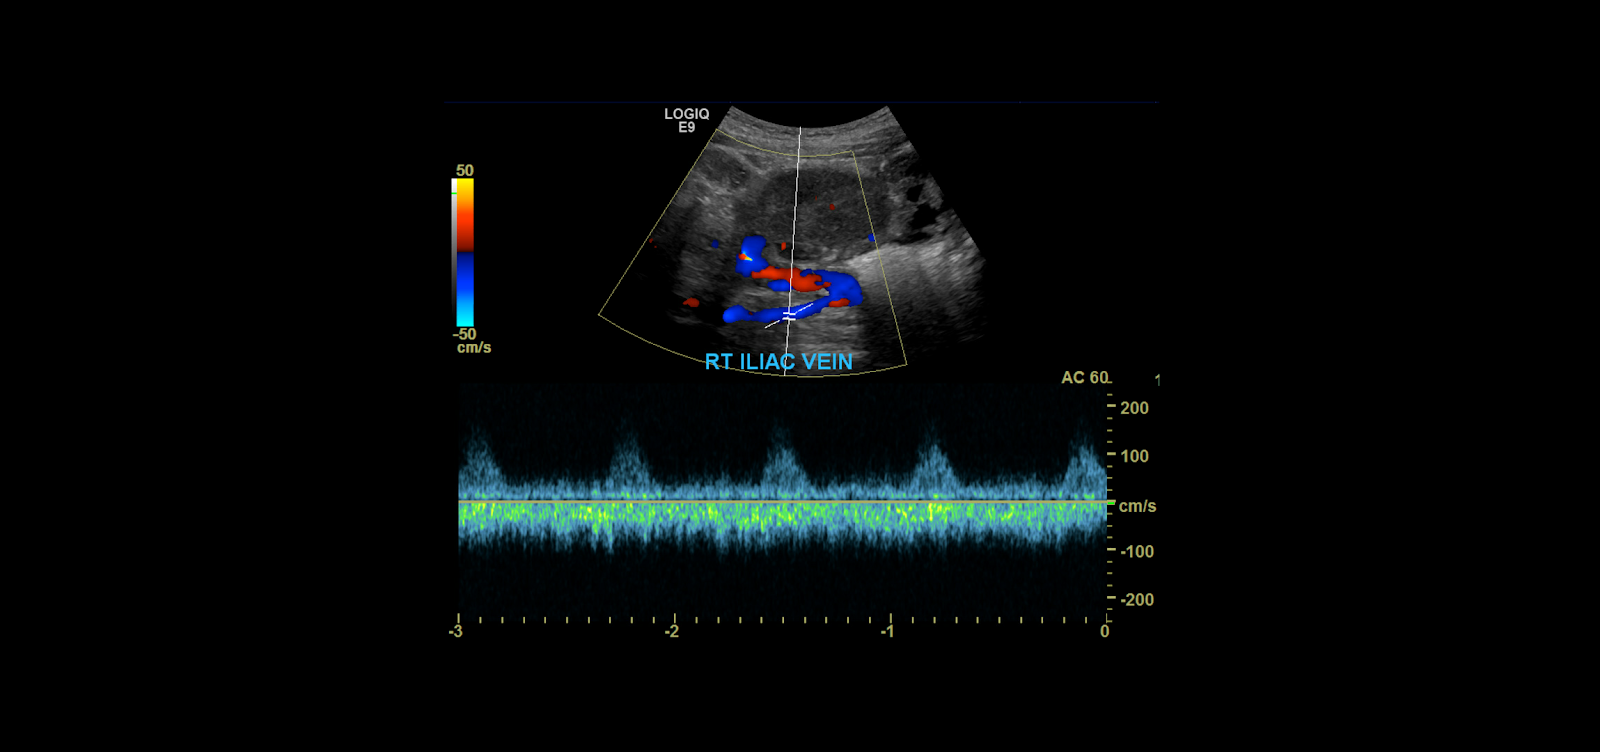

When you’re done examine the kidney in gray-scale you become to take your color spectral Doppler images. Begin with the iliac vessels.

Take gray-scale, color and spectral Doppler of the common iliac artery. Use angle correction 45-60°.

Measure the peak systolic and end diastolic velocities.